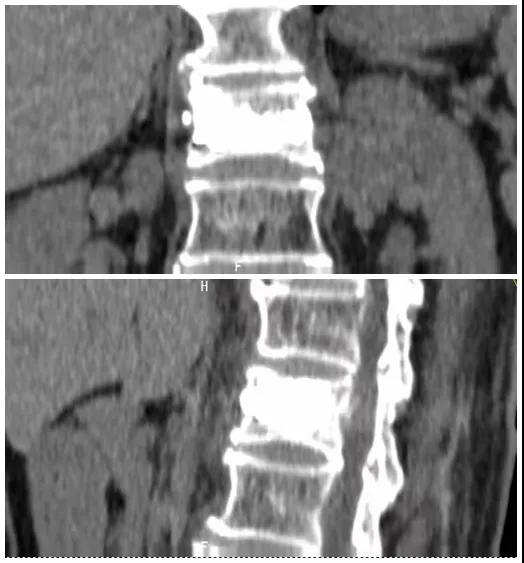

術前磁共振檢查提示腰1椎體新鮮壓縮性骨折

術后復查CT可見骨水泥彌散充分